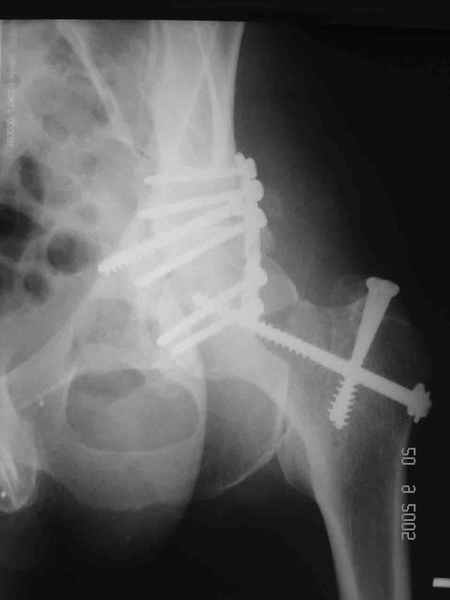

Привет! Вот недавно прооперировали похожий на ваш случай - впадина + шейка (правда у нас впадина поперечный+задний край). После травмы прошло 4 недели. мужчине 46 лет. С такой комбинацией все показания к первичному протезированию. Морально и технически мы к этому уже созрели.Но больной не собрал денег на протез. Выполнили остеосинтез впадины и шейки, прекрасно понимая, что головка вскоре рассосется, мы хотя бы надемся что к этому времени таз срастется, как говорится создали все условия для дальнейшего протезирования (может, и протез в последующем подешевле будет, в смысле, без укрепляющего кольца?). Привет Рункову!